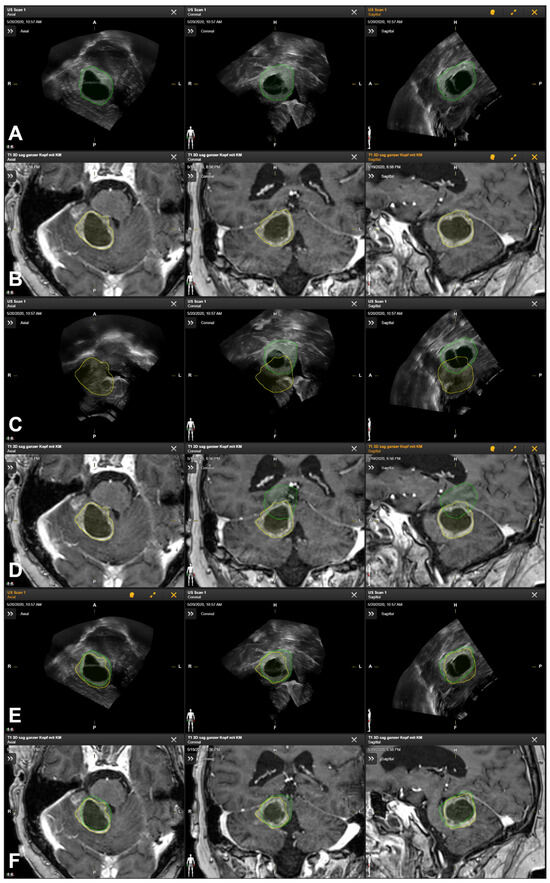

2.5. Intraoperative Navigated Ultrasound

2.6. Additional Postprocessing Using Rigid Image-Based Co-Registration

- Saß, B.; Carl, B.; Pojskic, M.; Nimsky, C.; Bopp, M. Navigated 3D Ultrasound in Brain Metastasis Surgery: Analyzing the Differences in Object Appearances in Ultrasound and Magnetic Resonance Imaging. Appl. Sci. 2020, 10, 7798. [Google Scholar] [CrossRef]